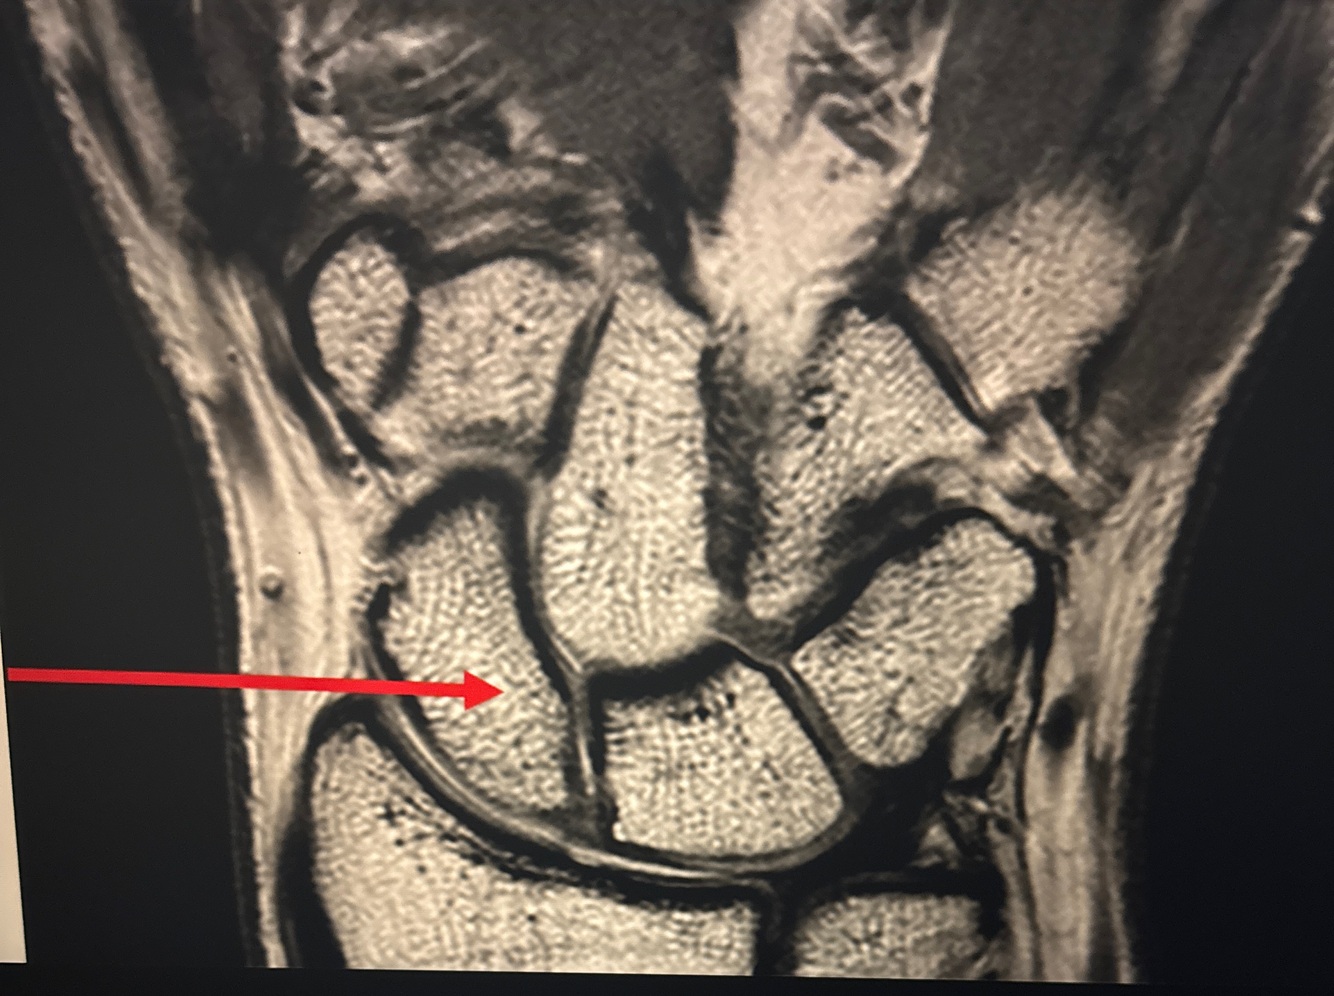

11

Q

A. Scaphoid

B. Pisiform

C. Triquetrum

D. Lunate

A

Lunate Triquetral Midcarpal joint Radiocarpal joint

A triquetral B midcarpal joint C lunate D radiocarpal joint